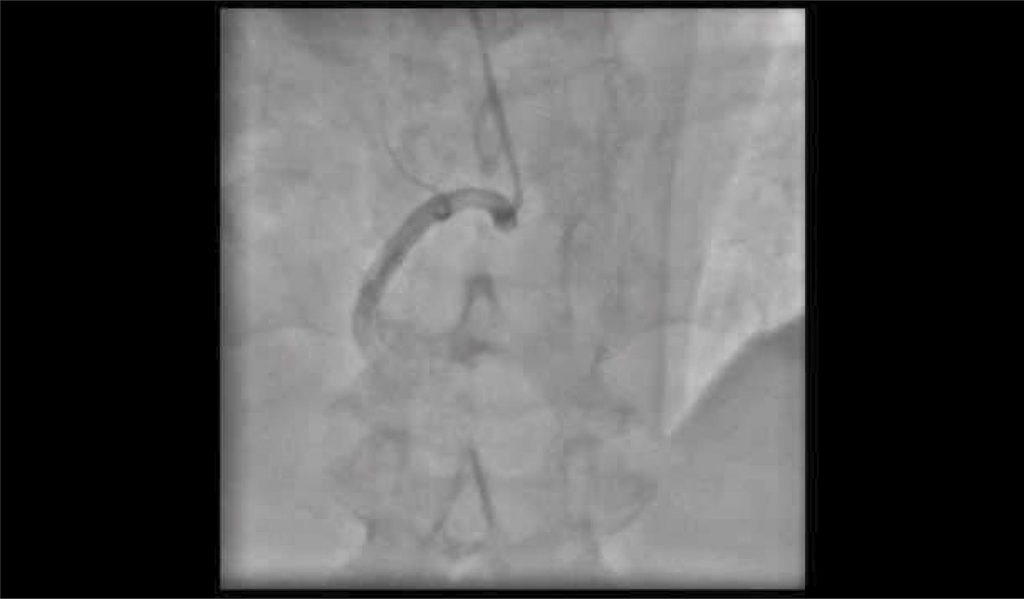

Video 1

Well-developed Rentrop 3 collaterals from right coronary artery to left anterior descending.